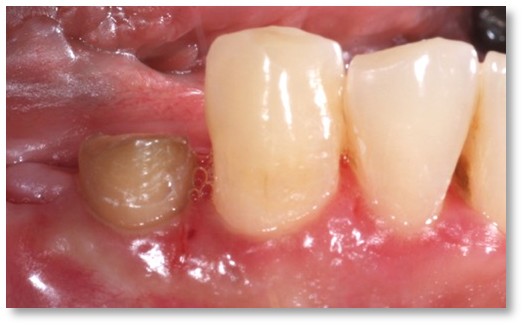

Before and after Periodontal Therapy

| Untreated severe gum disease | Gum disease treated and stabilised by Dr Halai |